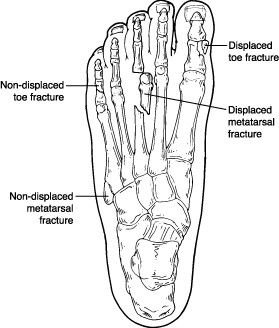

Traumatic fractures (also called acute fractures) are caused by a direct blow or impact, such as seriously stubbing your toe. Traumatic fractures can be displaced or non-displaced. If the fracture is displaced, the bone is broken in such a way that it has changed in position (dislocated).

Traumatic fractures (also called acute fractures) are caused by a direct blow or impact, such as seriously stubbing your toe. Traumatic fractures can be displaced or non-displaced. If the fracture is displaced, the bone is broken in such a way that it has changed in position (dislocated).